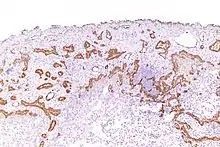

Using immunohistochemistry, calretinin can be demonstrated in both benign mesothelium and in malignant mesothelioma[12][13] and can be used to help differentiate different lung tumours.[14] Antibodies to calretinin can also be used to distinguish between different types of brain tumour, demonstrating only those with neuronal rather than glial, differentiation.[15] Furthermore, the essential function of calretinin in mesothelioma cell lines has been demonstrated in vitro and may be an interesting target for therapeutical approaches.[16]